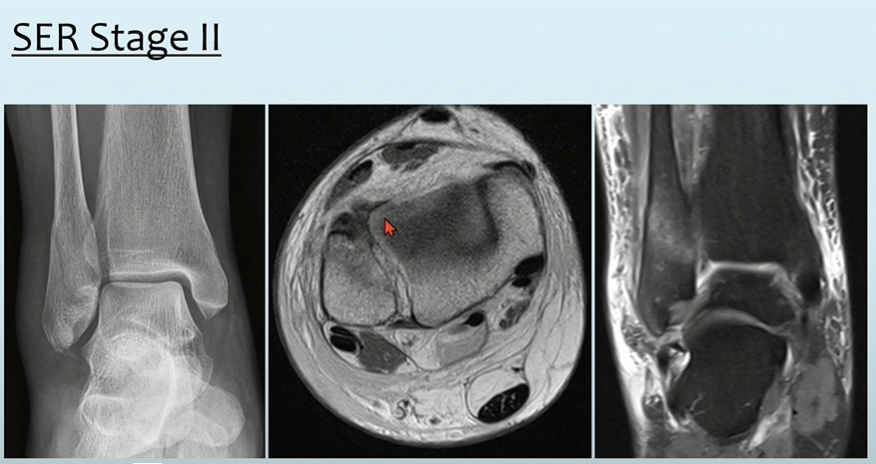

MRI상 ATFL injury 및 다른 영상에서 distal fibula에서 골절 소견이 있습니다.